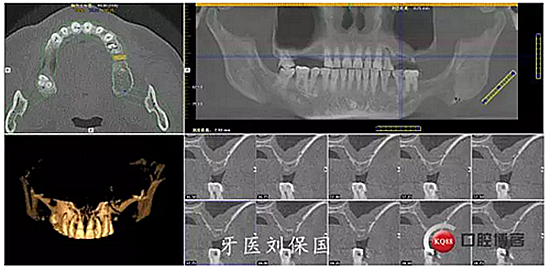

治療計劃及相關費用已向患者講明,征得患者同意,口腔及頜面部常規(guī)消毒,鋪巾,5.1ml必蘭局部浸潤麻醉下,切開,翻瓣,暴露牙槽骨,常規(guī)拔除患牙,清創(chuàng),沖洗,先鋒鉆定位,逐級擴孔,在25,26位置行上頜竇內(nèi)提術,植入bio-oss骨粉,在24,25,26位置分別植入Dentium 4.5*8mm植體各一枚,扭矩30Ncm,旋入愈合基臺 603R,縫合,沖洗。

3.術后CT: